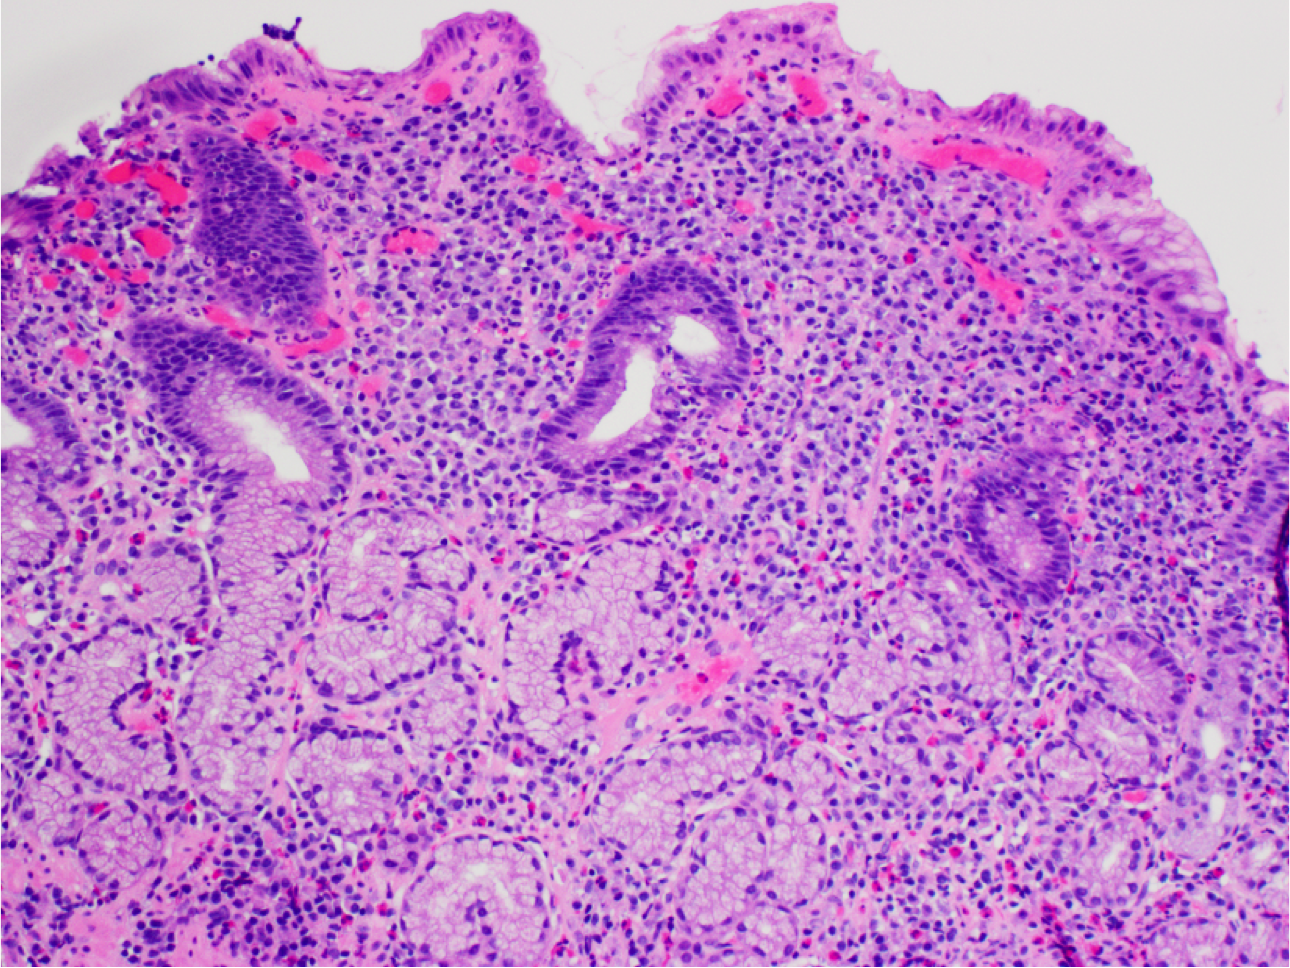

What’s this? What’s notable?

Barrett Esophagus.

Gastro-esophageal junction with columnar mucosa of intestinal type (intestinal metaplasia).

Goblet cells are present – note cells with large droplets of grey/blue mucin.

Also note maturation (increasing N:C ratio) of intestinalized epithelium towards the luminal surface of the crypts.